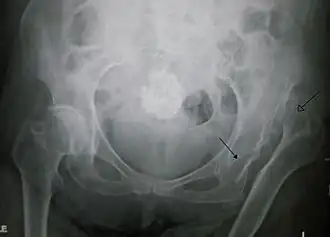

La luxation congénitale de la hanche est une affection du nouveau-né, symptomatique de dysplasie congénitale ou développementale de l'acetabulum.

Les anomalies chez le nouveau-né ou l'enfant connues sous le terme de dysplasie acétabulaire et subluxation ou luxation de la tête du fémur hors du cotyle (ou acetabulum), parce qu'ils sont présents à la naissance, sont longtemps étiquetées comme dysplasie ou luxation “congénitale” de hanche (Enseignement Hôpital Necker, Paris, Judet J. 1964)[source insuffisante].

Dépistage

La radiographie n’a plus sa place dans le dépistage jusqu’à 3 mois.